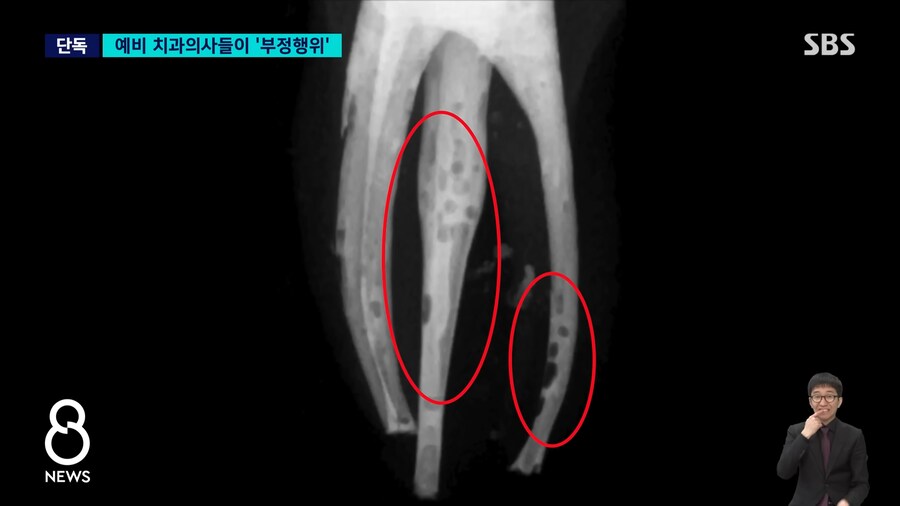

저기 구멍뚫린것 처럼 보이는 검은색이 신경치료하면서 충전제를

꼼꼼히 채워넣지 못한 부분..

교수에게 제출한 사진

포토샵등으로 검은 부분 메꿔서 제출...